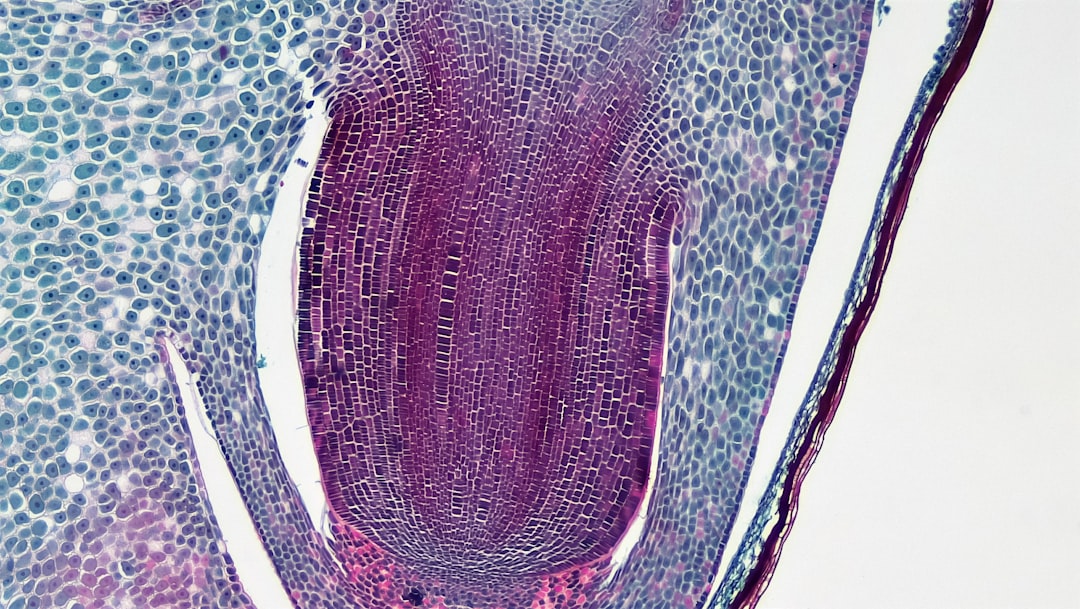

Revolutionary Gene Editing Techniques Unveiled

Advancements in the field of genetics are unlocking the secrets of our DNA and hereditary traits.